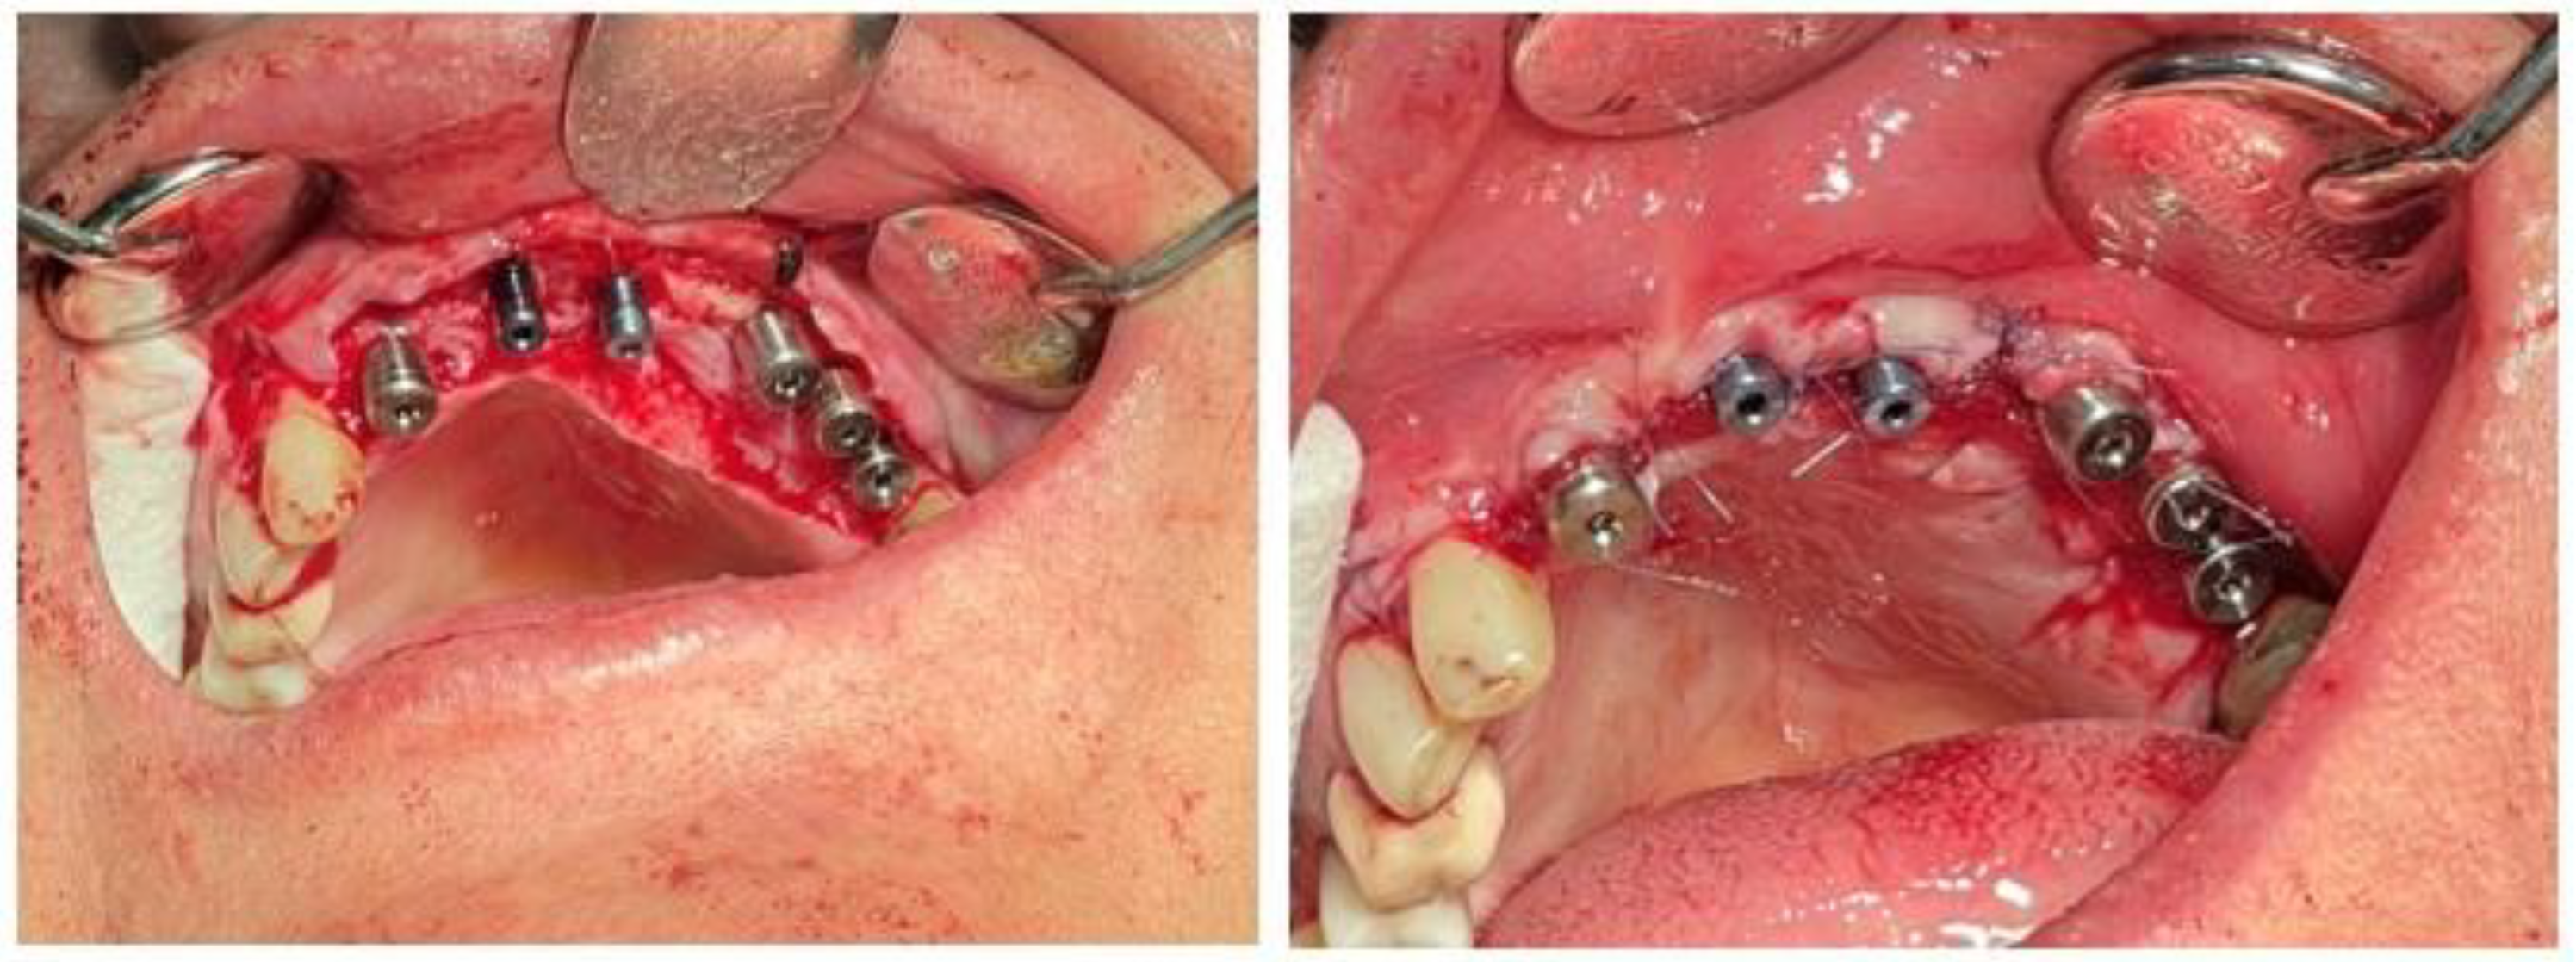

At six months post-augmentation, CBCT evaluation confirmed sufficient bone volume and density to proceed with implant placement. Six IRES Swiss implants were inserted according to the prosthetic plan: two 3.3 × 10 mm fixtures in the maxillary central incisor positions (teeth #1), one 3.3 × 8 mm fixture in the lateral incisor site (tooth #2), one 3.3 × 8 mm fixture in the first premolar site (tooth #4), one 3.7 × 8 mm fixture in the second premolar site (tooth #5), and one 3.7 × 10 mm fixture in the first molar site (tooth #6). Primary stability was achieved in all sites. The postoperative panoramic radiograph confirmed accurate three-dimensional implant positioning, parallelism, and intimate bone contact along the implant surfaces. The surgical procedure began with a crestal alveolar incision to expose the augmented ridge. Sequential osteotomy preparation and placement of IRES Swiss dental implants were performed according to the planned positions. Following implant placement, cortical cancellous allograft was applied around the implants to increase alveolar ridge width, which not only enhanced bone thickness but also improved labial support (Figure 8) .

Healing abutments were connected six months following implant placement Figure 10. The patient reported no pain, swelling, or complications during the 12-month follow-up period

Figure 8. Surgical stages of implant placement: (A) crestal alveolar incision; (B, C) sequential placement of IRES Swiss dental implants at planned sites; (D) application of cortical cancellous allograft around implants to increase alveolar ridge width and enhance labial support.

Figure 10. Placement of healing abutments six months after implant insertion to allow for proper soft tissue shaping prior to prosthetic phase.